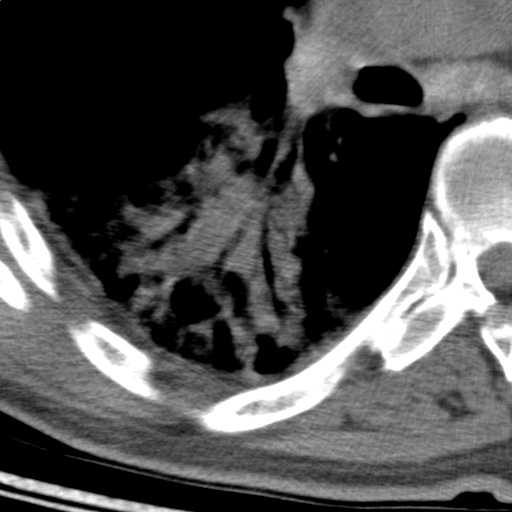

以下是引用随光逐影在2009-5-1 13:53:00的发言:[br]考虑为:1)两肺血行播散型肺结核;2)右肺下叶炎症感染。3)右侧胸膜增厚。